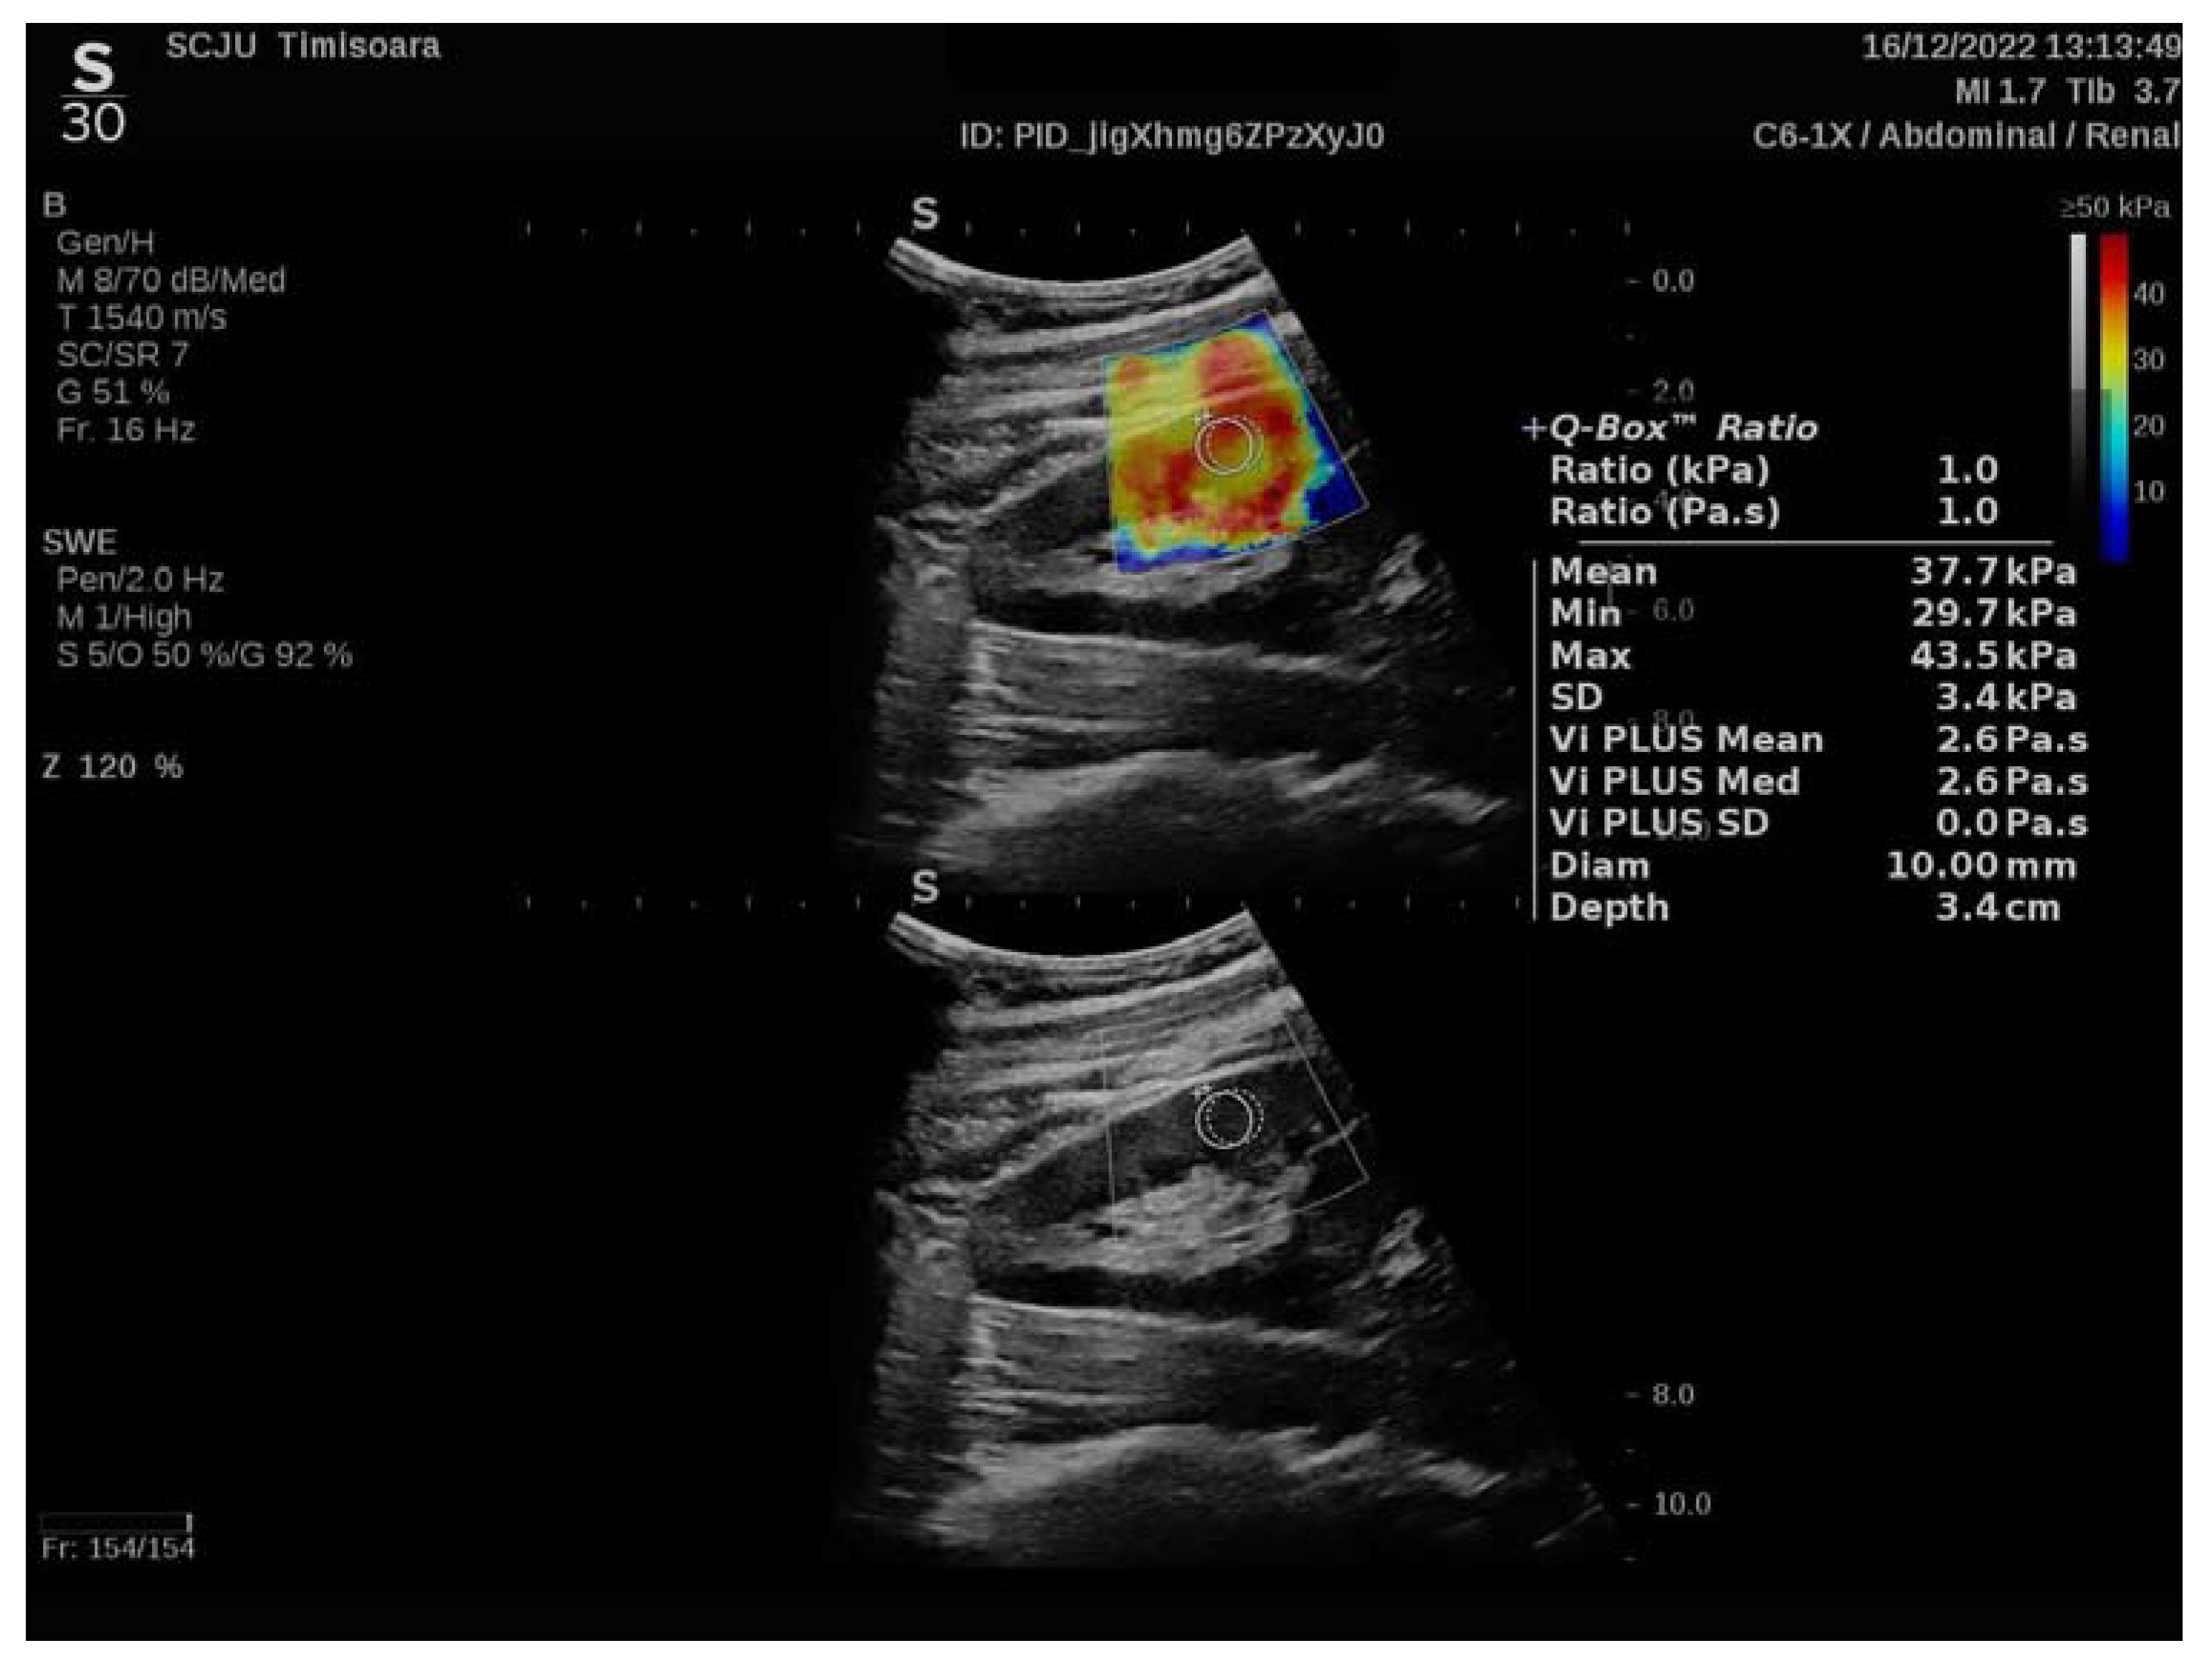

2.2. Elastography

- Maralescu, F.-M.; Bende, F.; Sporea, I.; Popescu, A.; Șirli, R.; Schiller, A.; Petrica, L.; Moga, T.V.; Mare, R.; Grosu, I.; et al. Assessment of Renal Allograft Stiffness and Viscosity Using 2D SWE PLUS and Vi PLUS Measures—A Pilot Study. J. Clin. Med. 2022, 11, 4370. [Google Scholar] [CrossRef] [PubMed]

- Maralescu, F.-M.; Bende, F.; Sporea, I.; Popescu, A.; Sirli, R.; Schiller, A.; Petrica, L.; Miutescu, B.; Borlea, A.; Popa, A.; et al. Non-Invasive Evaluation of Kidney Elasticity and Viscosity in a Healthy Cohort. Biomedicines 2022, 10, 2859. [Google Scholar] [CrossRef]